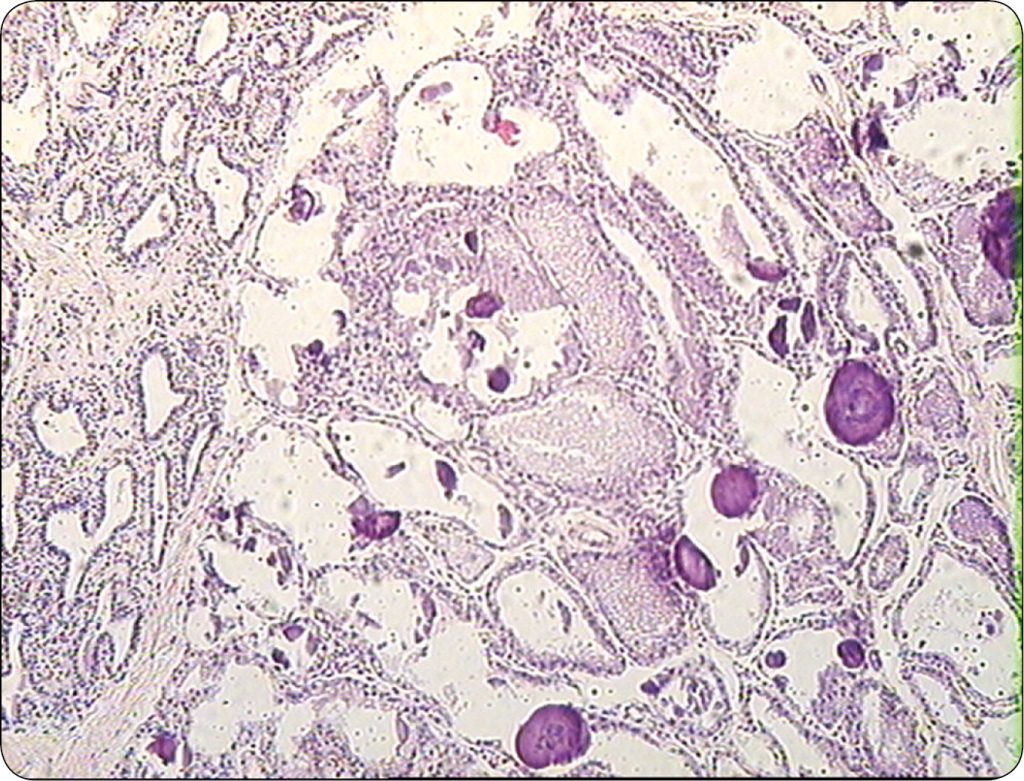

Uszkodzenie tkanki gruczołowej wyrażało się obecnością w strukturze komórkowej gruczołu mlekowego charakterystycznych cech patologicznych, a mianowicie były to: torbiele powstałe z pęcherzyków wydzielniczych, metaplazja apokrynowa komórek nabłonka gruczołowego, włóknienie zrębu gruczołu, proliferacja pęcherzyków, rozrost komórek nabłonka gruczołowego i komórek myoepitalialnych, rozrost gruczołowy (adenosis) z równoczesną proliferacją zrębu łącznotkankowego gruczołu, a także brodawczaki dużych przewodów gruczołowych. Wyrazem zalegania mleka pęcherzykowego jest obecność w świetle pęcherzyków gruczołowych, tzw. ang. milk calcium, czyli inkrustowanej solami wapnia wydzieliny gruczołu. Niektóre z wymienionych typów zmian patologicznych stwierdzonych w gruczole mlekowym krów chorych na adenomyosis/endometriosis ilustrują ryc. 2 i 3. Podobne zmiany patologiczne stwierdzano w gruczole sutkowym suk, u których ponadto występowały różnego typu guzy nowotoworowe (7).

Należy podkreślić, że zmiany patologiczne stwierdzano we wszystkich badanych ćwiartkach gruczołu mlekowego krów chorych na adenomyosis/endometriosis, przy czym były one różnorodne u [...]